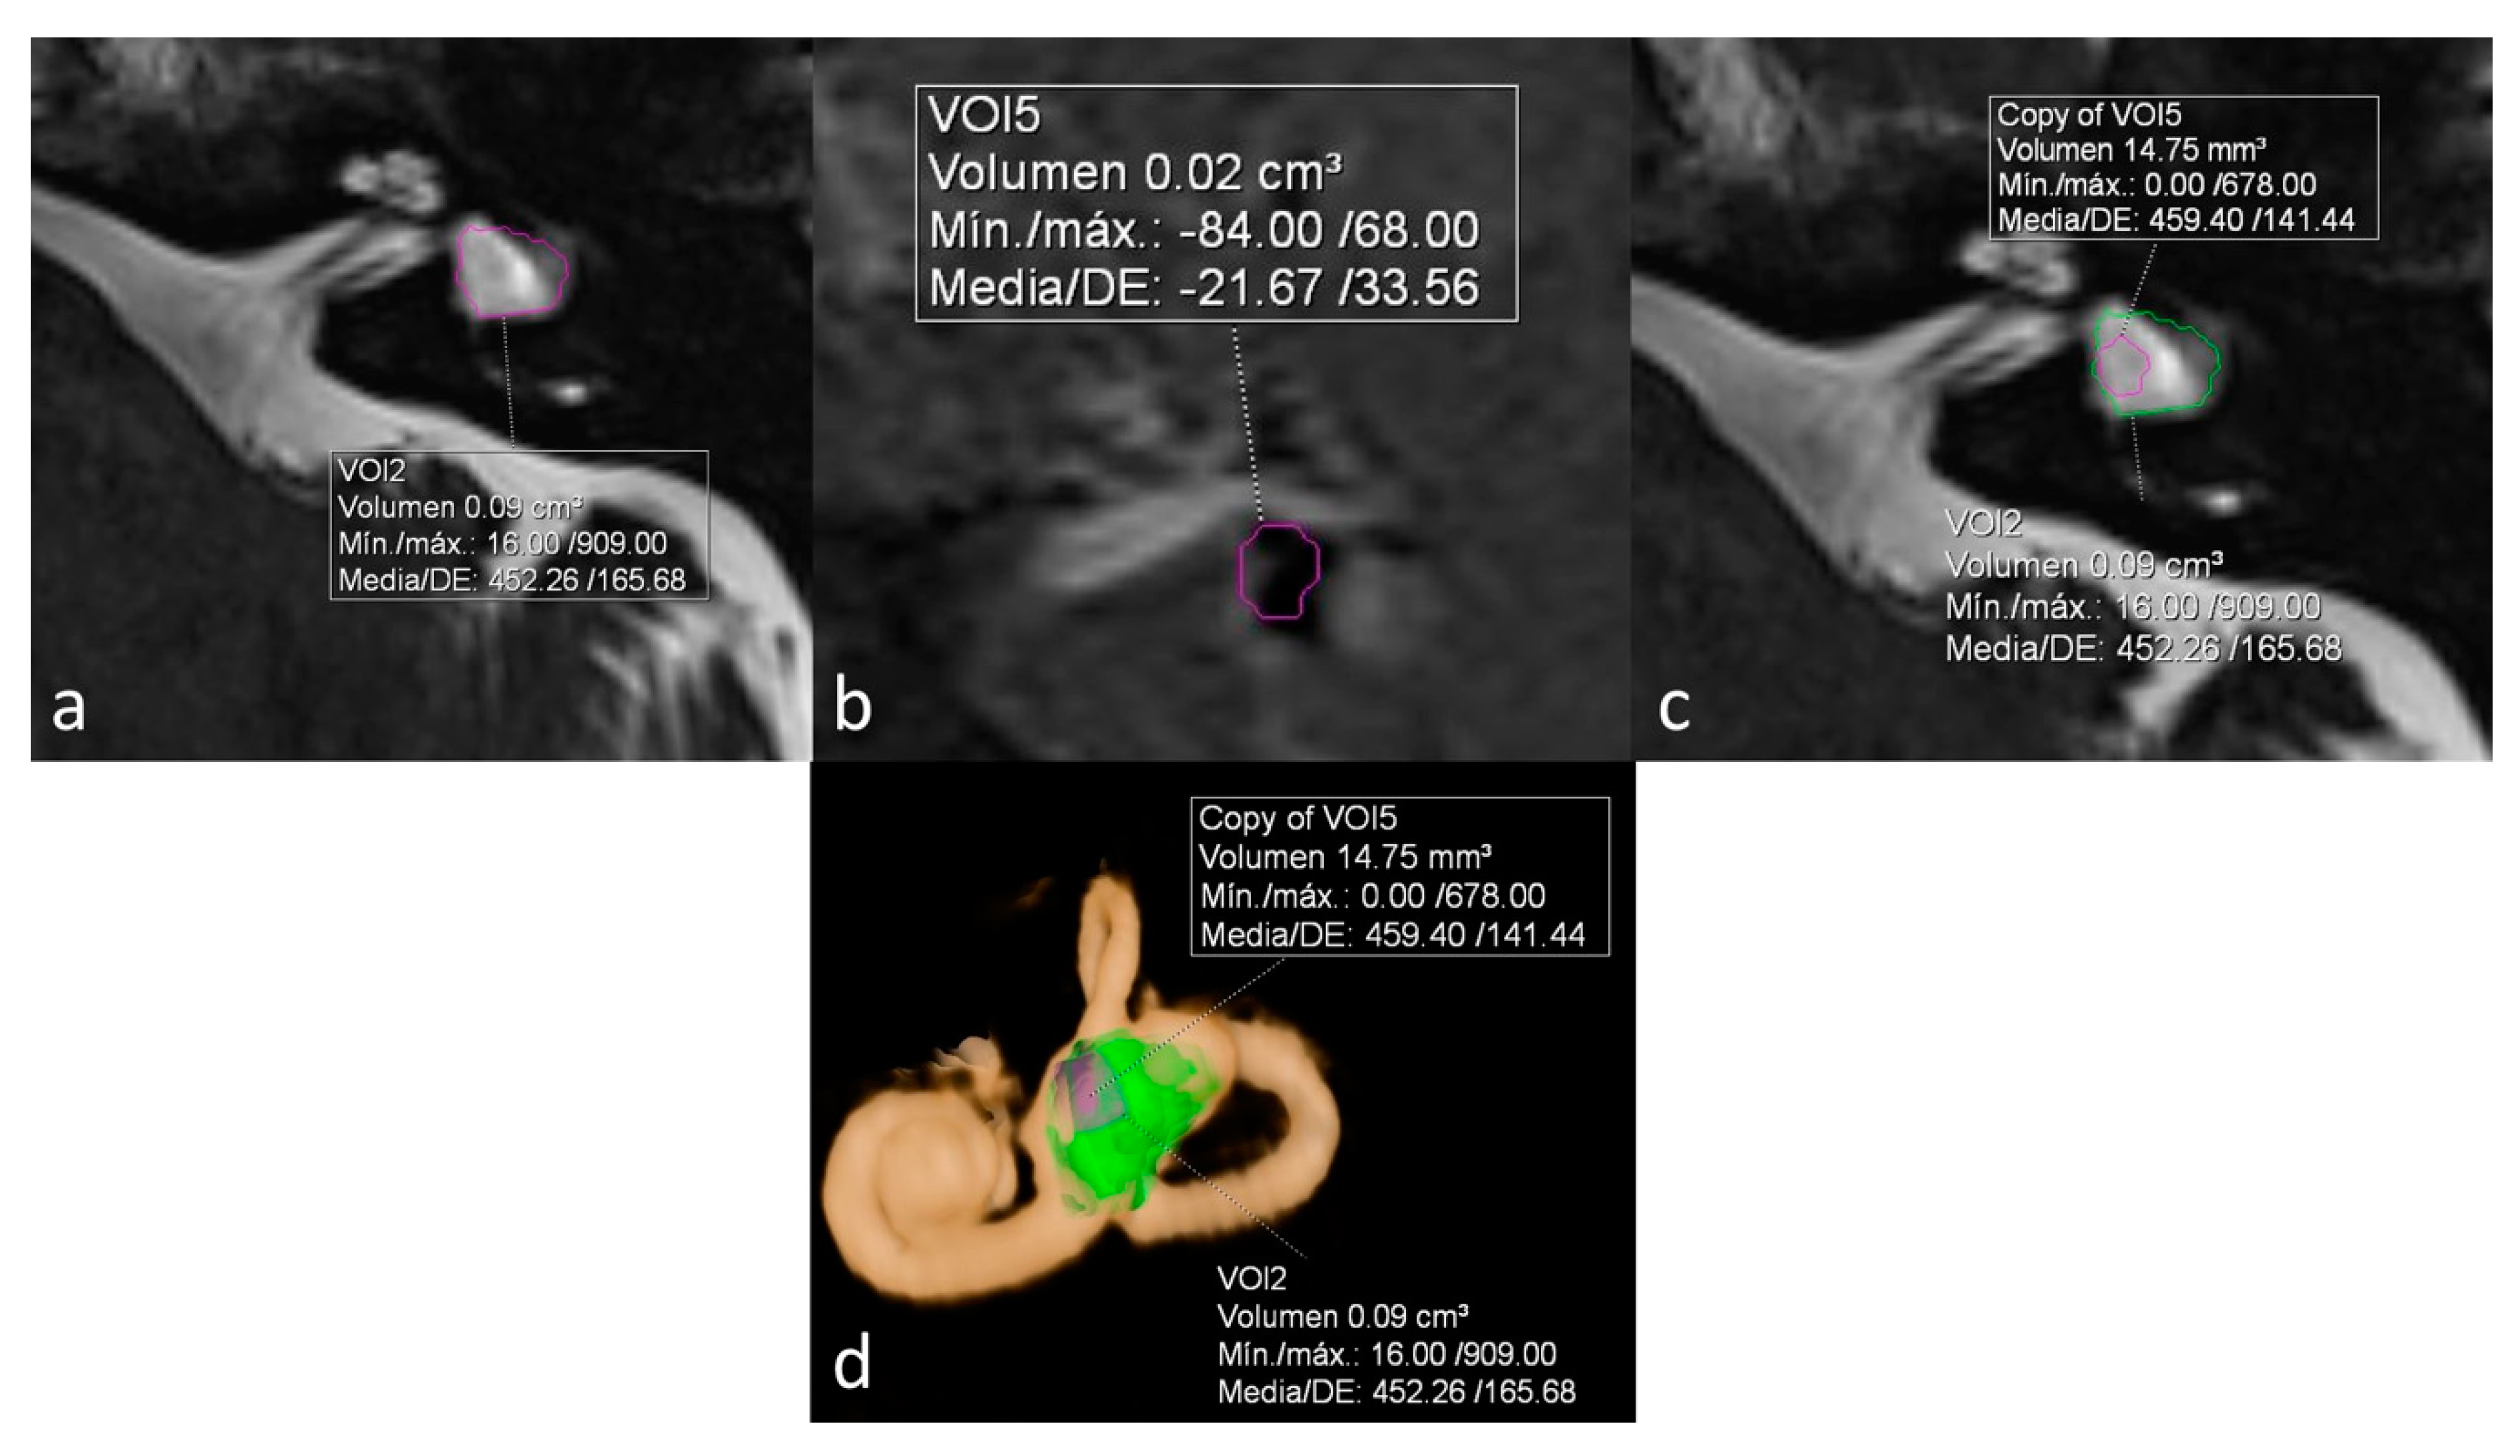

On a dedicated workstation with Syngo.via software (Siemens Healthineers, Erlangen, Germany, Client version 5.1), we used the MR cisternography sequence (T2 3D SPACE) to measure the total volume of vestibular lymph fluid (bright signal) on diseased ears defined as bright signal within the cystoid cavity formed by the union of the vestibule and the aplastic LSCC in a semi-automatic fashion. An experienced radiologist manually delineated the boundaries of the vestibule in all slices, and the software automatically calculated the total volume. As no central bony islands were depicted, no subtractions to this total volume were needed. The total volume of endolymph within the cystoid cavity was also calculated semi-automatically using the 3D-IR with REAL reconstruction sequence manually tracking the low signal in the vestibule. The endolymphatic volumetric ratio (ELR) [9] was calculated as the total vestibular endolymphatic volume divided by the total vestibular cavity volume multiplied by 100. The radiologist was not aware of the clinical information during the process of volume segmentation (Figure 1).

Figure 1.

Sequences used for the calculation and depiction of endolymphatic and total vestibular volumes and endolymphatic ratio (ELR). (a) Heavily T2 weighed cisternography sequence depicts lymph within a right cystoid lateral semicircular canal (LSCC). A semi-automatic calculation of total vestibular lymph volume is shown. (b) 3D-IR-REAL hydrops sequence depicts low signal (dark) vestibular endolymphatic volume. (c) 3D volume-rendered image of the inner ear based on the cisternography sequence with color coded overlay of both vestibular and endolymphatic hydrops volumes.

The other two patients, both with unilateral LSCCD, showed intermediate percentages. One patient was suffering from hearing loss without vestibular symptoms (patient 3) and showed an ELR of 33% (shown on Figure 1). The other patient had symptoms of probable MD (patient 6) and showed an ELR of 42% (not shown).